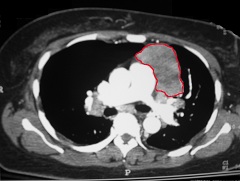

Лимфаденопатия или увеличение лимфатических узлов данного органа наблюдаются при метастазах карциномы, лимфомах, а также некоторых неопухолевых заболеваниях (саркоидозе, туберкулезе и т.д.).

Поражение лимфатических узлов, характерное для лимфом может быть изолированным, так и сочетать собой прорастание опухолей в другие анатомические структуры (трахею, сосуды, бронхи, плевру, пищевод, легкие).